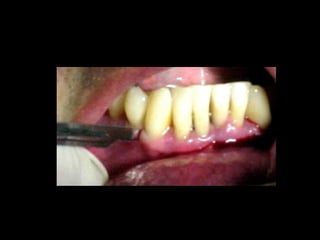

La periodontitis, denominada comúnmente piorrea, es una enfermedad que

inicialmente puede cursar con gingivitis, para luego proseguir con una pérdida de

inserción colágena, recesión gingival, e incluso la pérdida de hueso, en el caso de

no ser tratada, dejar sin soporte óseo al diente. La pérdida de dicho soporte

implica la pérdida irreparable del diente mismo.

De etiología bacteriana que afecta al periodonto (el tejido de sostén de los dientes,

constituido por la encía, el hueso alveolar, el cemento radicular y el ligamento

periodontal) se manifiesta más comúnmente en adultos mayores de 35 años, pero

puede iniciarse en edades más tempranas.

Periodontitis

•Zerón Agustín. Nueva clasificación de las enfermedades periodontales. ADM. 2001; LVIII(1):16-20.

Clasificación

Una periodontitis según su grado de afectación dental se clasifica en: leve,

moderada o grave. Y según su extensión se denomina: localizada o

generalizada.

Las periodontitis desde 1999 se han clasificado (ASP) en: crónicas,

agresivas y asociada a estados sistémicos.